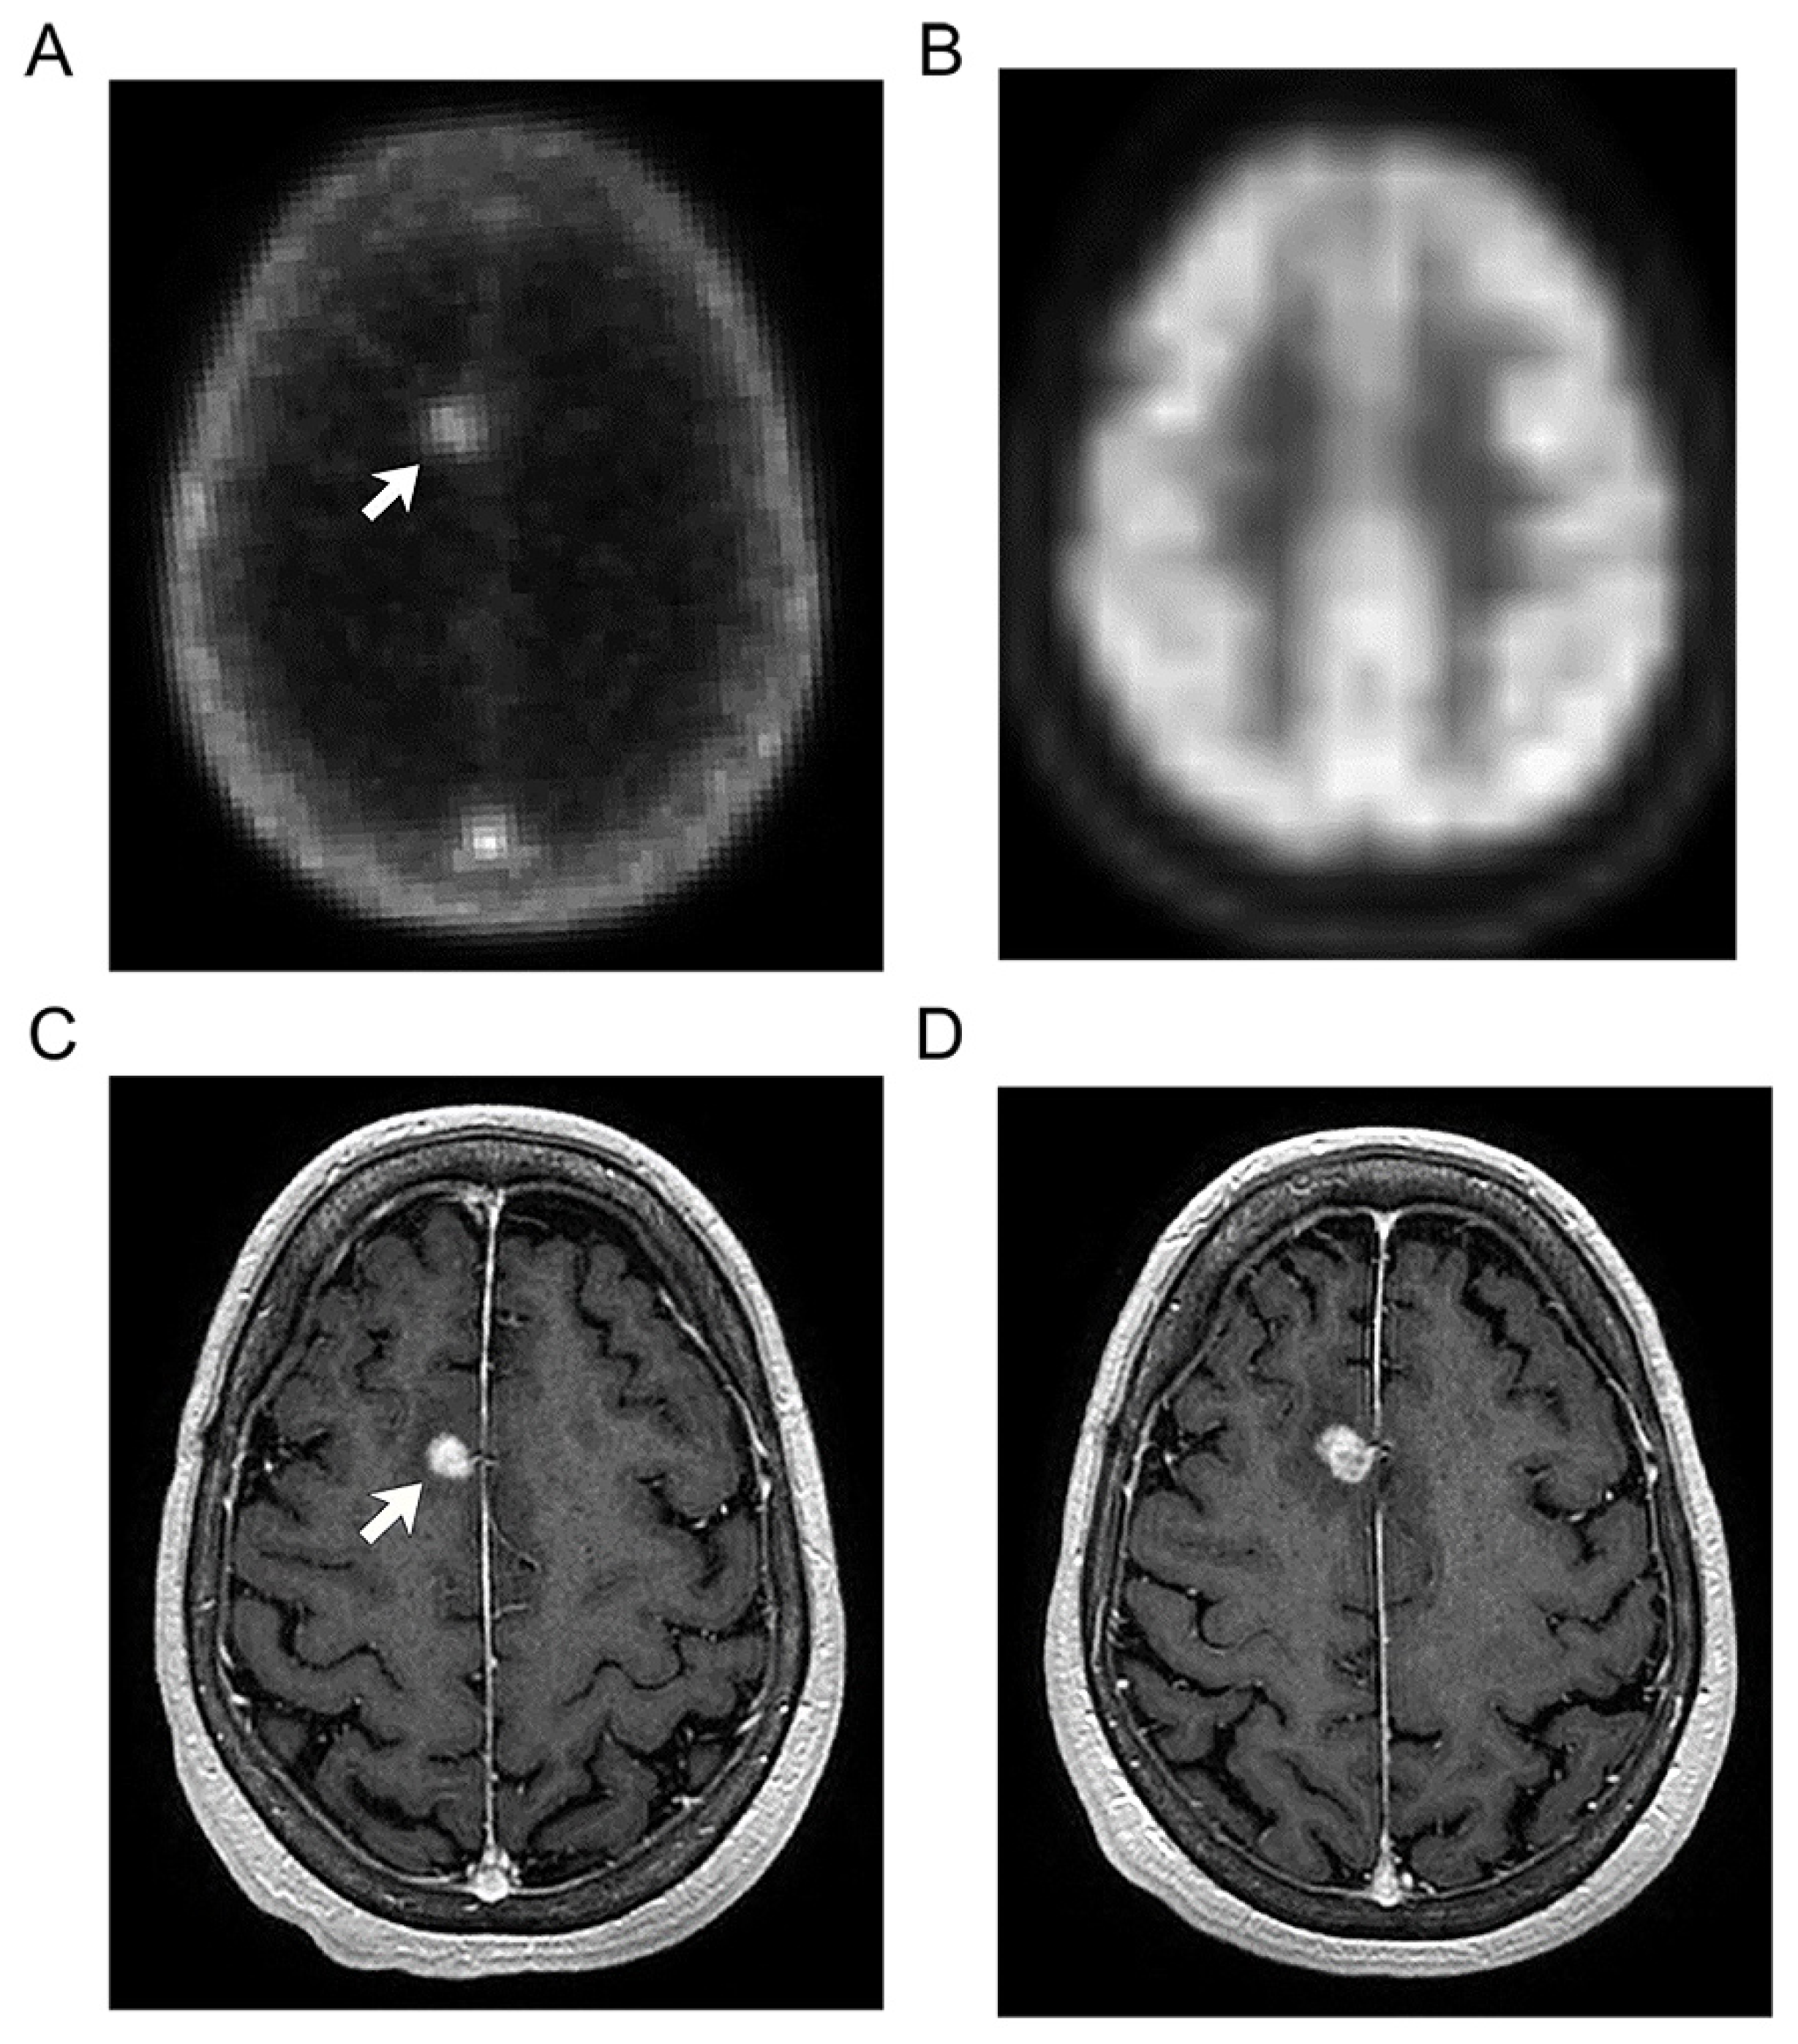

In another case, increased [124I]I-NM404 uptake matched with a small focus of abnormal enhancement in the right frontal lobe on MR in a patient who previously underwent resection and subsequent stereotactic radiosurgery for metastatic melanoma (Figure 2). No abnormal uptake was seen in this area on the concurrent clinical [18F]FDG PET study (Figure 2B). Based on the clinical MR and [18F]FDG PET findings, distinction between radiation necrosis and tumor recurrence was not possible. However, at subsequent follow-up MR imaging (Figure 2D), the nonspecific enhancing lesion has continued to enlarge, associated with progressive perilesional edema, more concerning for metastatic disease.

Figure 2. Recurrent brain metastasis in 60-year-old woman with malignant melanoma. [124I]I-NM404 (A) and [18F]FDG (B) PET images 8 months after stereotactic radiosurgery for tumor recurrence of a right frontal falcine metastasis shows a focus of abnormal activity with NM404 (arrow) but no detectable abnormality with [18F]FDG. Corresponding enhancing focus on MR imaging ((C), arrow) was interpreted as radiation necrosis versus possible recurrence. Subsequent MR imaging (D) showed further increase in size of the nonspecific enhancing lesion, coupled with increased perilesional edema. Patient remains in close-interval imaging surveillance.